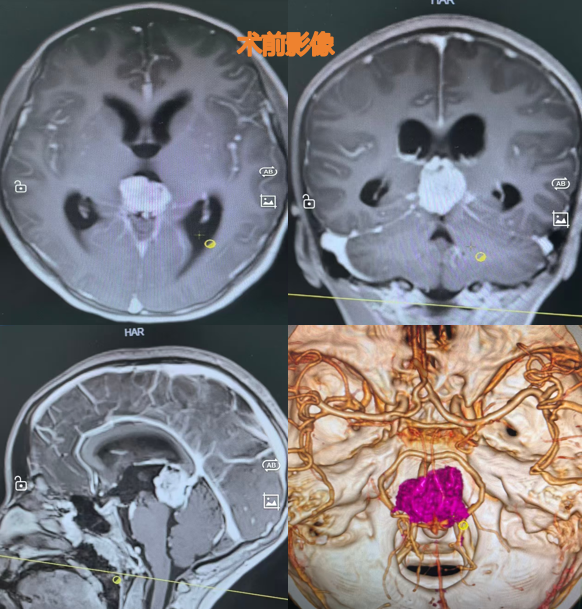

该院神经外迅速组织了神经内科、肿瘤科、影像科及病理科等多学科会诊,认为该病疑似为松果体区生殖细胞恶性肿瘤同时伴有梗阻性脑积水。

按照治疗指南,首先要进行开颅手术取得病理活检标本,同时解决梗阻性脑积水问题,缓解颅内高压,为后续治疗争取时间。由于肿瘤血供极为丰富,术中情况极不稳定,继续操作将显著增加出血、脑损伤等风险。为保障患者安全,团队及时调整手术策略,中止切除,并依据术中脑组织肿胀情况,去除部分颅骨骨瓣,以缓解颅内压力,为后续康复治疗创造条件。

但时间不等人。再次检查时发现,小汪的肿瘤体积较术前有所增大,经过专家组综合研判,最终决定采用伽玛刀放射治疗。

据龚飞龙介绍,选择伽玛刀放射治疗为当时最可行的方案。彼时,小汪术后情况还不稳定,需要心电监护及氧气吸入等设备支持,无法承受多次普通放疗。同时,手术没有取得病检标本,诊断不明确,无法制定详细的化疗方案。与之相比,伽玛刀具有单次剂量高、治疗周期短的优势。

为缩短单次治疗时间,保证小汪安全,龚飞龙决定用伽玛刀分两次放射治疗,中间间隔5天。幸运的是,首次伽马刀放射治疗后,小汪的检查结果显示其脑肿瘤体积缩小了50%。两次伽马刀放射治疗后,脑肿瘤体积缩小了80%。